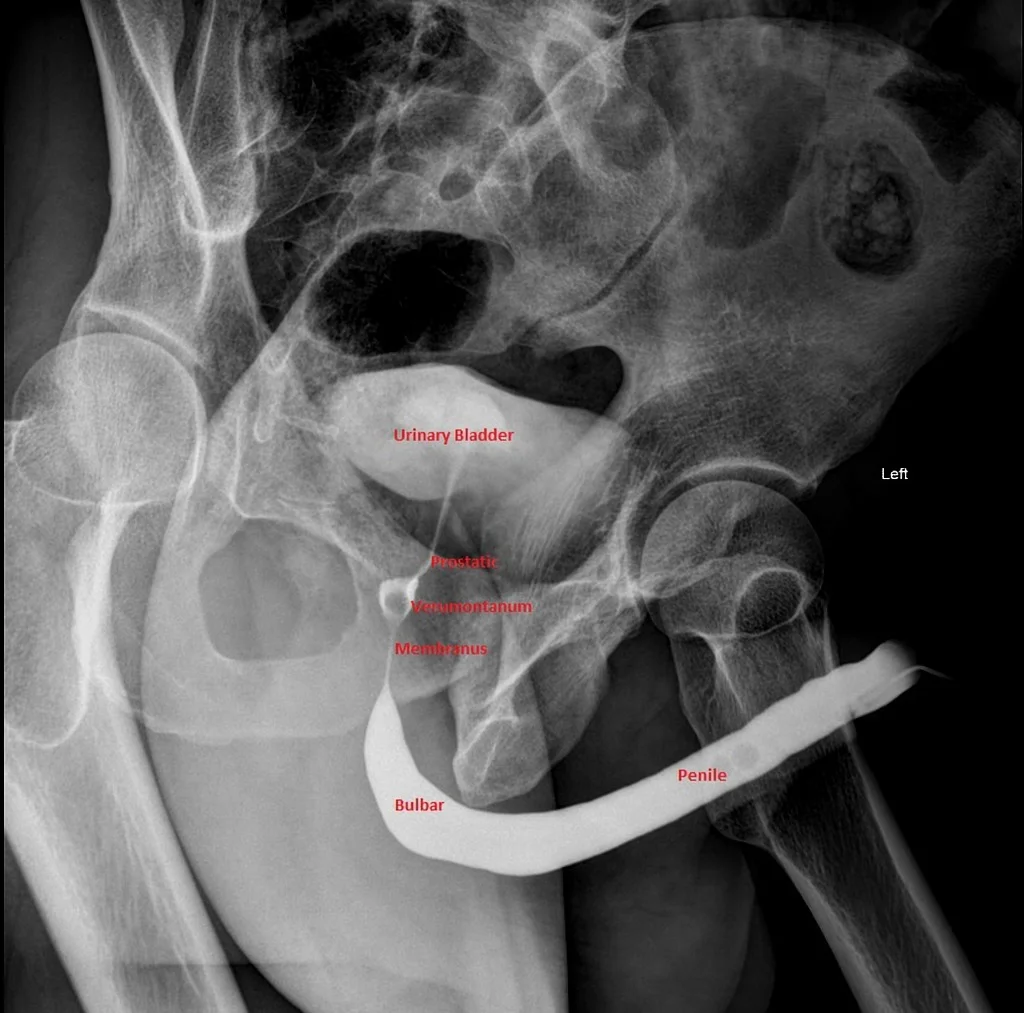

/It is early on in your residency training, when you receive sign-out of a patient who was involved in an MVC with multiple injuries including a stable pelvic injury. The patient, a middle-aged male, has not voided three hours into his visit and there is no mention of any obvious genital trauma. He has had a negative FAST exam in addition to the rest of your primary and secondary assessment. The patient mentions to the nurse that he is trying to urinate but cannot void and has some discomfort. The bladder scan shows that the patient has about 500cc of urine and when the nurse goes to place a urinary catheter she pauses as she sees what appears to be dried blood at the urethral opening. After reassessing the patient who is still hemodynamically stable with normal mentation, his findings are discussed with Urology who recommend getting a retrograde urethrogram prior to any additional procedures.